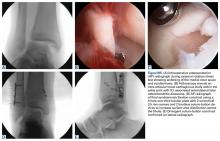

In American football players, we have observed that infolding and retraction of an avulsed superficial deltoid ligament complex after an ankle fracture, Maisonneuve injury, or severe high ankle sprain can be a source of persistent increased medial clear space, malreduction, and postoperative pain and medial instability. We have found that there is often complete avulsion of the superficial deltoid complex off the proximal aspect of the medial malleolus during high-energy ankle fractures in football players that is amenable to direct repair to bone (Figures W6A-W6E).

In a cohort of 14 NFL players who underwent ankle fracture fixation with ankle arthroscopy and debridement, fibula fixation with plate and screws, syndesmotic fixation with suture-button devices, and open deltoid complex repair with suture anchors, all athletes were able to return to running and cutting maneuvers by 6 months after surgery.35 There were no intraoperative or postoperative complications noted, and no players had clinical evidence of medial pain or instability at final follow-up with radiographic maintenance of anatomic mortise alignment.During surgical repair, an incision is made along the anterior aspect of the medial malleolus and the superficial deltoid ligament complex can often be found flipped and interposed in the medial gutter. A rongeur is used to create a bleeding cancellous bone surface for soft-tissue healing and 1 to 2 suture anchors are used to repair and imbricate the deltoid ligament complex back to the medial malleolus. The goal of these sutures is to repair the tibionavicular and tibial spring ligaments back to the medial malleolus. We believe that superficial deltoid complex avulsion during high-energy ankle fractures is a distinct injury pattern that should be recognized and may benefit from primary open repair.